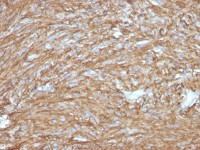

Immunohistochemical analysis of paraffin-embedded human adrenal cortical tumor, using RIC8A(GTX107712) antibody at 1:100 dilution.

Antigen Retrieval: Trilogy™ (EDTA based, pH 8.0) buffer, 15min